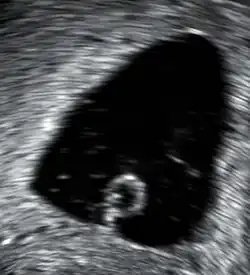

Ein Ultraschalluntersuchung zeigt einen Gestationssack, der einen Dottersack enthält, aber keinen Embryo.

Abortivfrucht

Dies ist eine Fehlentwicklung eines befruchteten Eis, bei der die Embryonalanlage verkümmert ist oder ganz fehlt. Die Abortivfrucht (auch Windei genannt) geht in den ersten Schwangerschaftswochen zugrunde. Bei 50–90 % der Spontanfehlgeburten im 2. Schwangerschaftsmonat handelt es sich um ein Abortivei. Als Ätiologie werden neben genetischen Defekten auch äußere Faktoren wie Intoxikation und Sauerstoffmangel erwogen. Die Gebärmutter wächst nicht. Subjektive Schwangerschaftssymptome sind nur schwach ausgeprägt, teils bestehen Schmierblutungen. Die Diagnose wird nach einer Ultraschalluntersuchung gestellt. Die Schwangerschaftsanlage misst meist weniger als 3 cm. In der von Chorionzotten umgebenen leeren Fruchtblase befindet sich kein Embryo (obwohl sich seit 1995 mit modernen Ultraschallgeräten auch manchmal kleine Embryoblasten sichtbar machen lassen; möglicherweise handelt es sich dann um frühe Formen des verhaltenen Abortes). Als Therapie kommt eine Kürettage in Betracht, es kann aber auch der natürliche Abort abgewartet werden.